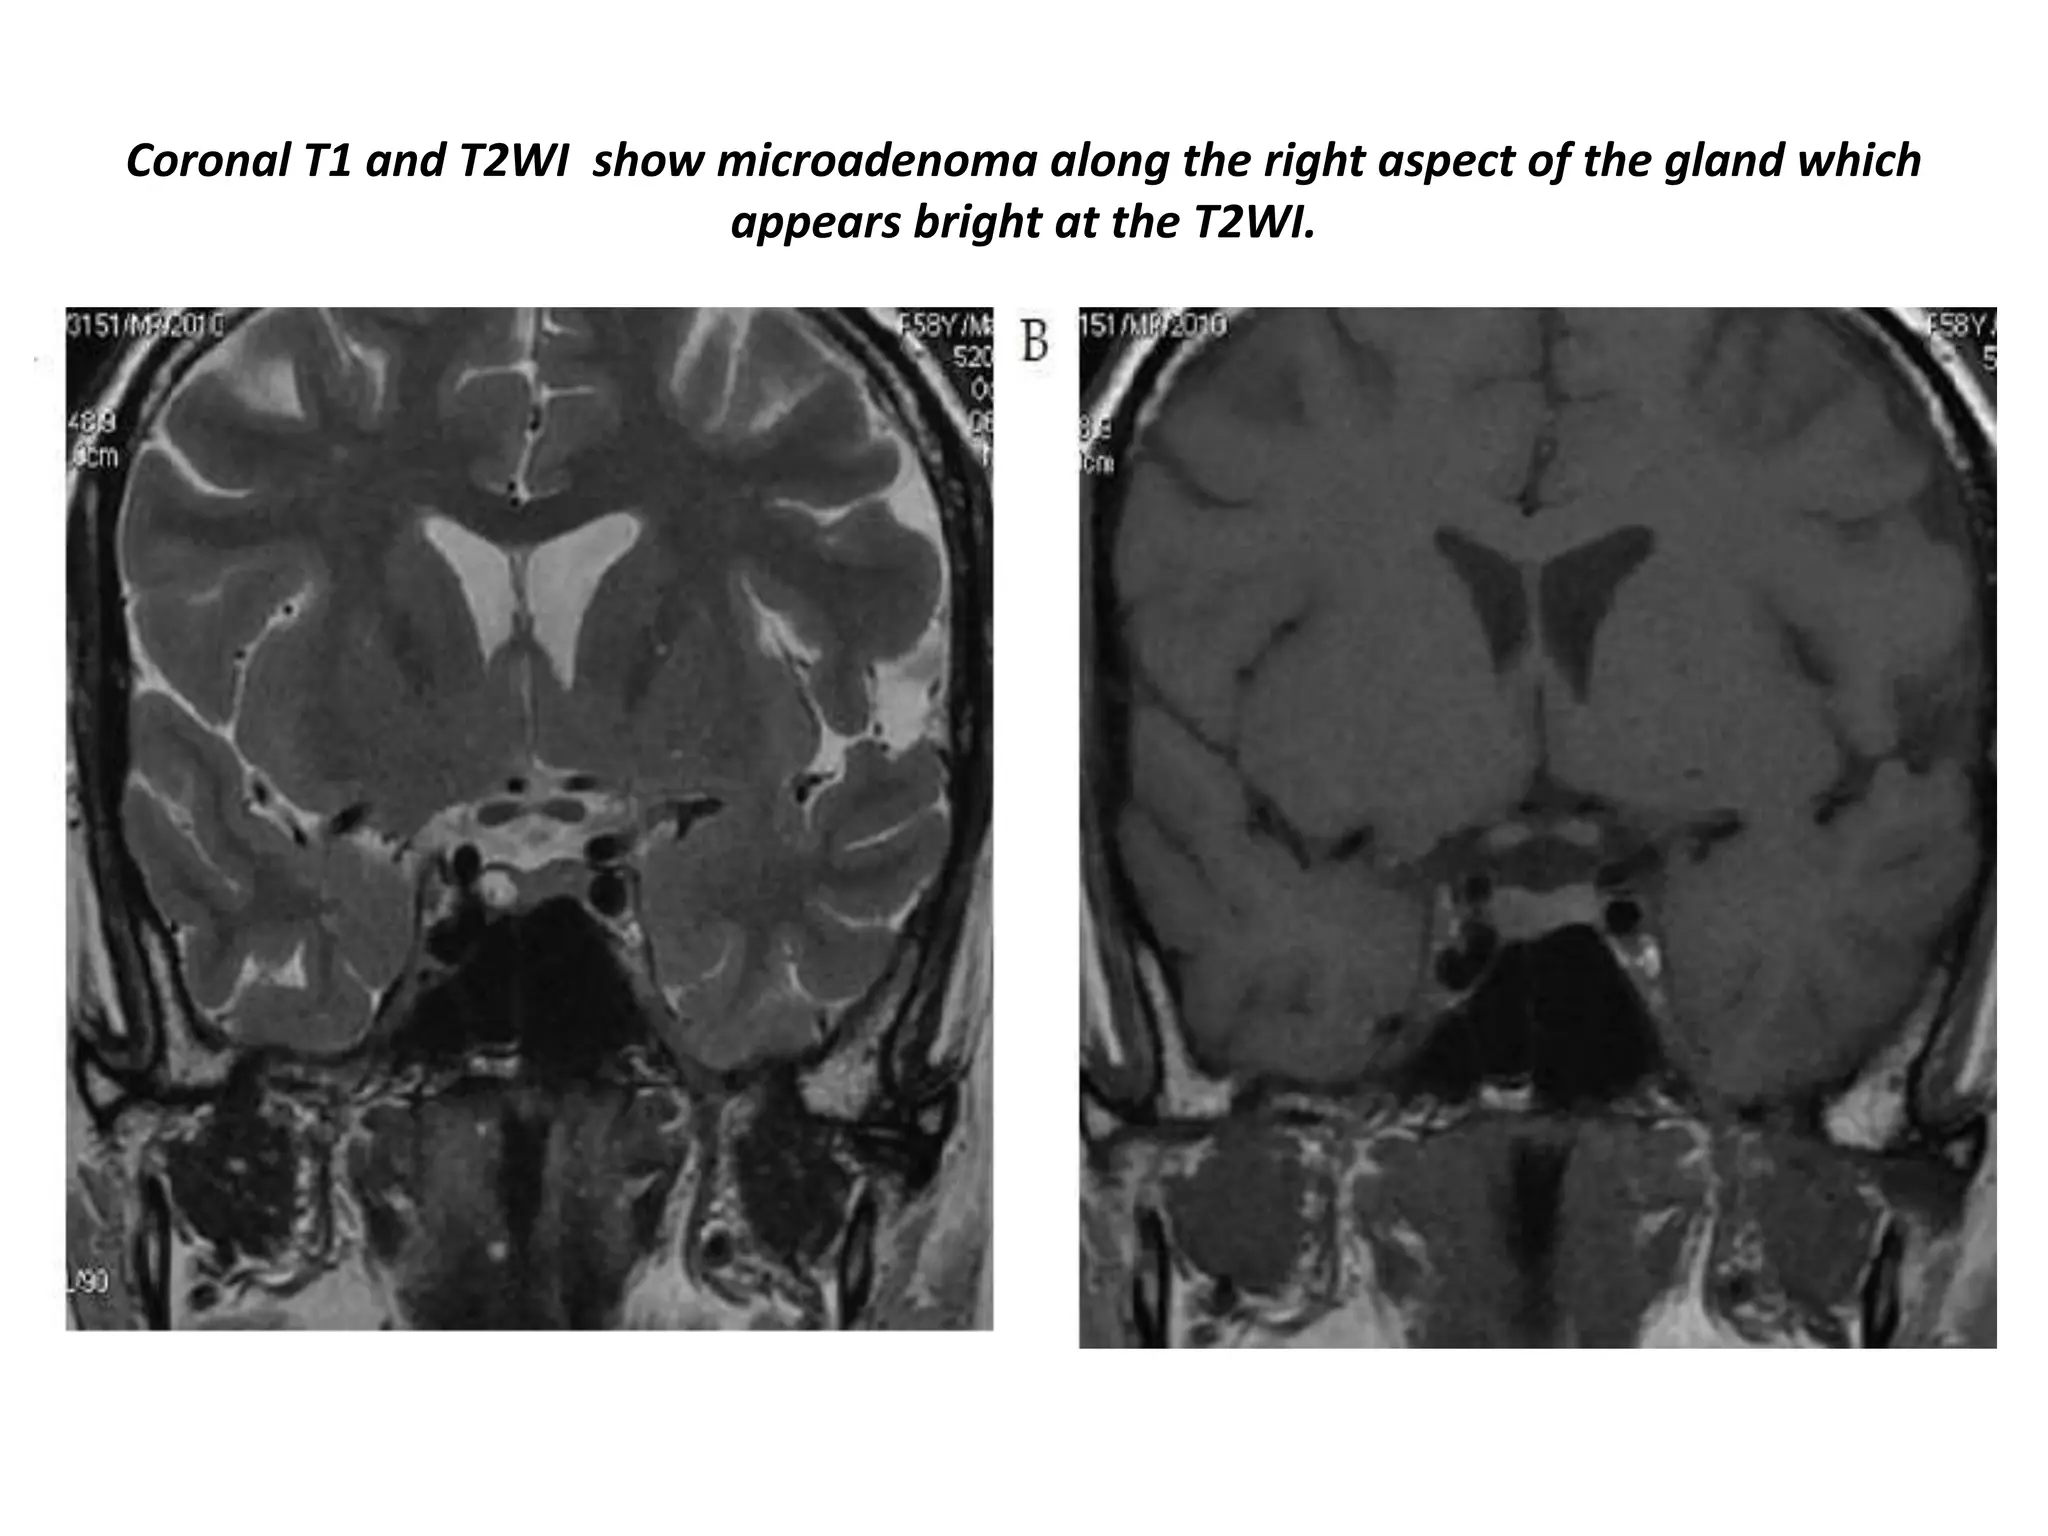

Coronal T1 and T2WI show microadenoma along the right aspect of the gland which

appears bright at the T2WI.

Post-contrast coronal T1WI shows hypointense microadenoma along the right aspect of the gland.

Delayed sagittal images after 10 minutes shows enhancing microadenoma is more clear.